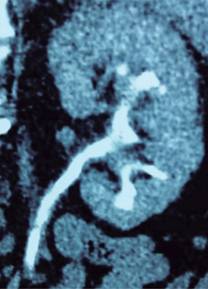

Figura 1: Imagen de tomografía computarizada. Reconstrucción coronal a nivel de riñón izquierdo en fase eliminatoria que evidencia atrofia cortical con predominio en polo inferior, con llenado incompleto e irregularidad de los cálices.

Figura 2: Imagen de tomografía computarizada. Reconstrucción 3D abdomino-pélvica en la que se observa irregularidad de los cálices renales con predominio izquierdo, así como disminución del tamaño del mismo con respecto al derecho.